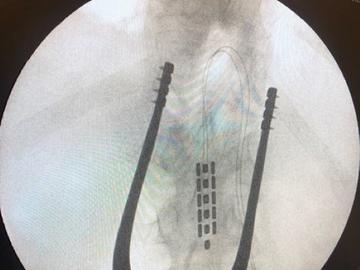

Epidural Spinal Cord Stimulation

What it is

Epidural stimulation describes a process where electrical current is applied to the spinal cord. Stimulation is applied through a small implant that is placed over the dura (protective layer around the spinal cord). For people with spinal cord injury, stimulation is applied below the level of injury. The intervention is typically a 45-minute outpatient procedure (statement by Neurosurgeon Dr. Darrow, U Minnesota). To date, stimulation has resulted in a wide array of benefits. For example, we recently published work showing that stimulation allowed volitional motor function below the level of injury for people with clinically-complete injuries of more than 5-10 years. This was achieved without rehabilitation and occurred the first time we turned stimulation on. Of course, rehabilitation is likely crucial to maximize the benefits of the stimulation. We have also observed reductions in bowel time, improved sexual function, improved lower-urinary tract function, more stable blood pressure, and increased exercise capacity.

How it works

In almost all clinically-complete injuries there are some preserved connections across the site of injury, but these connections are not functional in a normal state (i.e., dormant). By applying electrical current to the nervous system circuits within the spinal cord below the level of injury, we are able to re-awaken these dormant connections. This functional re-connection allows for the brain to recover some of the lost control over systems below the level of injury. Furthermore, the spinal cord is not simply a relay pathway (i.e., highway) transmitting information from the brain to the periphery. It also contains intricate interconnections that can process information and coordinate outputs with little input from the brain. Stimulation also helps to re-awaken these complex interconnections. Together, the awakening of dormant pathways and activation of complex interconnections with stimulation often leads to meaningful improvements in function for people with spinal cord injury. We are harnessing these concepts to provide health solutions for people with spinal cord injury.